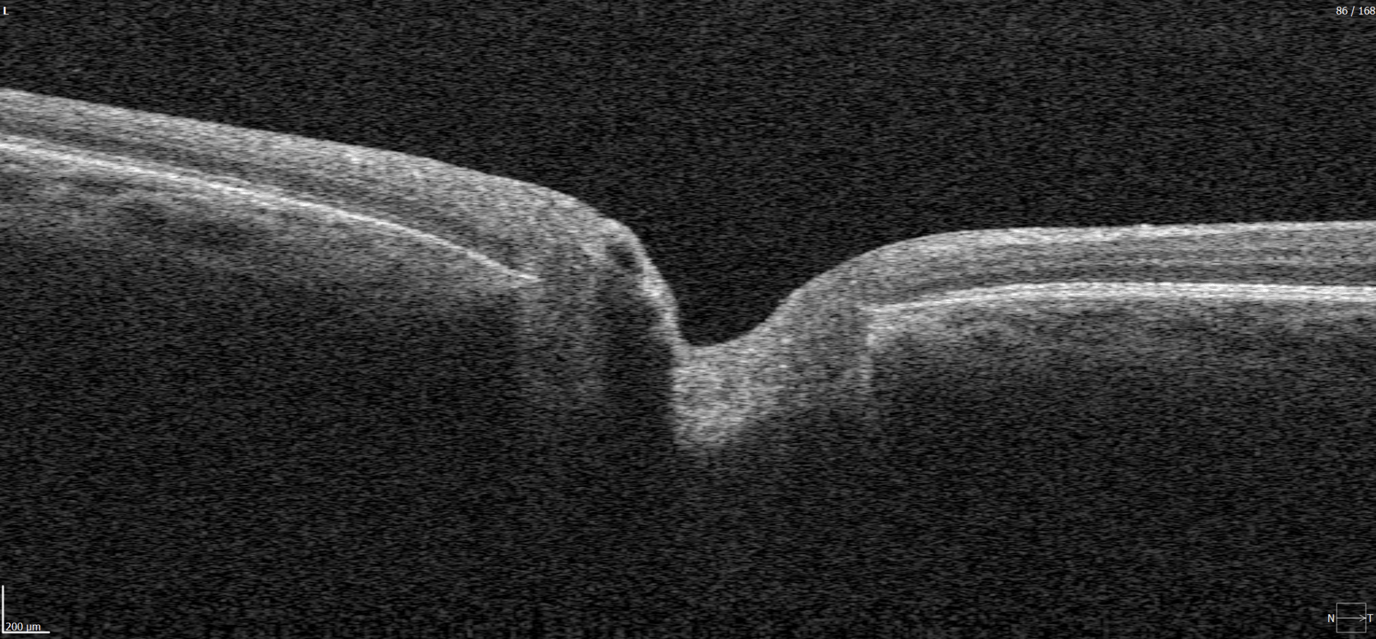

OCT has become a golden standard for diagnosing and monitoring many ocular pathologies, thanks to its unparalleled level of detail in ophthalmic imaging.

While retinal reports vary among OCT models, they typically include:- a foveally centered B-scan,

- a quantitative thickness map,

- and a semi-quantitative thickness map.

The B-scan offers a visual snapshot of foveal architecture and confirms proper scan centering. The quantitative thickness map employs the ETDRS sector map to measure retinal thickness within a 6mm circle around the fovea, with specific measurements for the foveal sector (1mm), inner macular ring (3mm), and outer macular ring (6mm).

Progression analytics enable comparison of serial macular scans, which is invaluable for managing vitreomacular interface disorders and macular edema. The semi-quantitative thickness map provides a broader overview of retinal thickness throughout the scan.

Given this amount of data, it is challenging to identify subtle and localized retinal pathological changes. As a result, entire OCT datasets are represented by few aggregated values, and the standard OCT reports generated by most devices often rely on significant data reduction to simplify interpretation, which you can usually not customize.

In current clinical practice, macular damage assessment typically involves measuring the distance between the ILM and RPE layers, summarized in a post-scan report.

However, these reports often fall short of visualization best practices, employing ineffective or inconsistent color schemes. Additionally, they lack flexibility, with static visuals preventing in-depth examination of specific details. Despite these limitations, these reports remain valuable for many clinicians by distilling complex data into a manageable format.